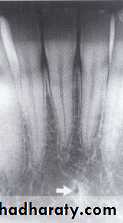

LINGUAL FORAMEN

:

The lingual foramen is a tiny opening or hole in the bone located on the internal surface of mandible, its located near the midline and surrounded by genial tubercle. Radiographically, the lingual foramen appears as small radiolucent dot located inferior to the apices of mandibular incisor.

NUTRIENT CANALS

Nutrient canals carry a neurovascular bundle and appear as radiolucent lines of fairly uniform width. They are most often seen on mandibular periapical radiographs running vertically from the inferior dental canal directly to the apex of a tooth or into the inter dental space between the mandibular incisors.